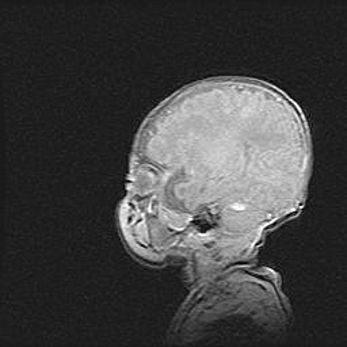

Наружная гидроцефалия с возможной атрофией височных областей.

Возраст: 28 дней

Вес: 3670 г

Пол: мужской

Окружность головы: 38 см

Срок гестации: 40 недель

Гидроцефалия головного мозга у новорожденных – это заболевание, которое характеризуется скоплением избыточного количества спинномозговой жидкости в желудочковой системе головного мозга в результате затруднения её перемещения от места выработки к месту поглощения в кровеносную систему или вследствие нарушения абсорбции. При открытой наружной форме гидроцефалии у новорожденных расширяются и переполняются субарахноидные пространства.

При нормотензивных  формах,  которые,  как  правило,  являются  следствием  перенесенных ишемических  повреждений  паренхимы  мозга,  возможно  сочетание микроцефалии  с нормотензивной гидроцефалией. В основе данных изменений лежит атрофия больших полушарий с преимущественной  локализацией  в  лобно-височных  областях.